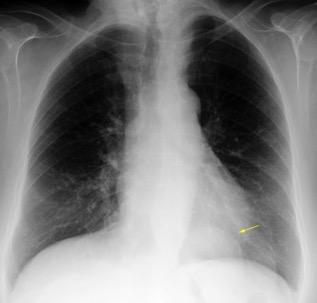

25. ELEVACIÓN UNILATERAL. TEP

Tromboembolismo pulmonar Diafragma elevado 20%